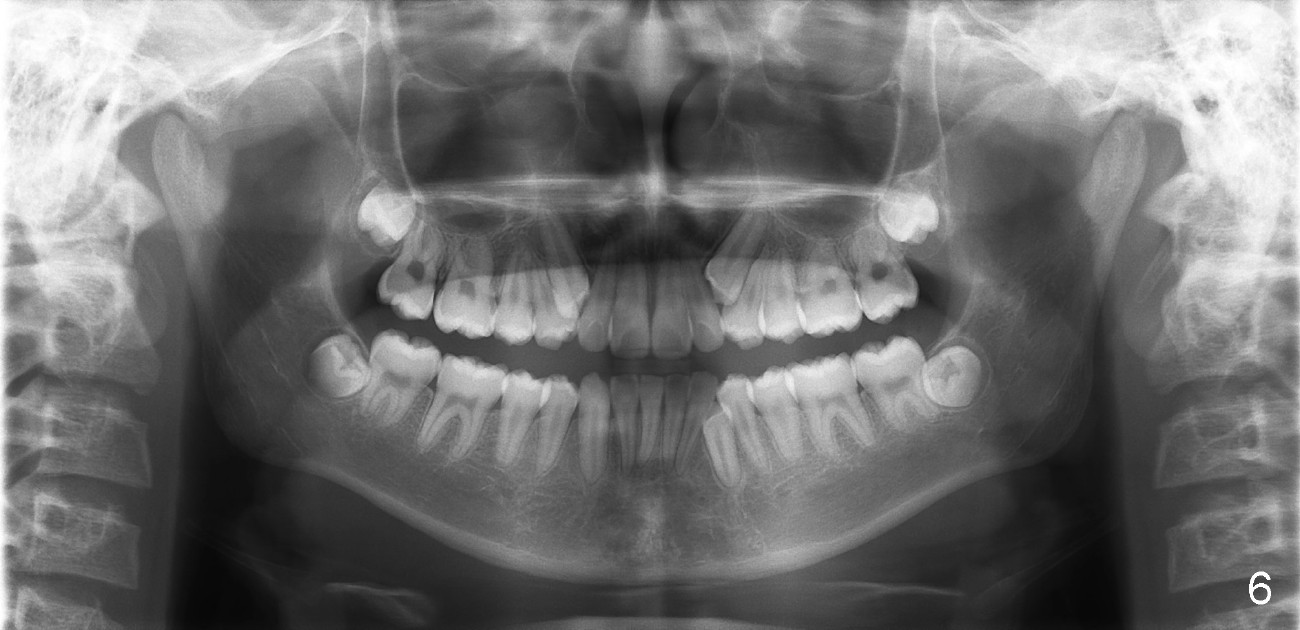

Please extract 5 and 12 in the maxilla, AND #22 in the mandible.  Yes, that is correct.  For a variety of reasons I am choosing to remove this tooth, i.e., mechanical advantage, less risk of bite opening, etc.  I also gave thought to extraction of #23 instead of #22 but the root length also points to the canine for extraction.  Bottom line, nothing made me NOT willing to extract #22, under these special circumstances.  Call me if you would like to discuss.

I also meant to mention that Toby has short roots generally and that is another reason why I wanted to be very efficient/minimize tooth movement in the lower.  In the upper arch, it is very worth it to retrieve the canines because of their superior root length.

Interdigitation in the posterior will be hard to achieve.  Primary goal in Toby is to resolve crowding and with short roots, be realistic.  A functional posterior occlusion is the goal. Something must be removed from the bottom and I am choosing to substitute the LL4 for a LL3:-)  And you are right, the LL3 is a bit longer than it appears on the pan because of imaging.

In fact, the canine was easier to be extracted than the two upper first bicuspids.  It had been nonfunctional, out of occlusion.  The periodontal ligament must be loose and alveolar bone is immature.  The buccal bony plate is thin and low.  Toby returned for cleaning 3 days post extraction.  The three sockets healed so well that photos were taken.  Unfortunately the latter are misplaced.  Otherwise we would share them with you.